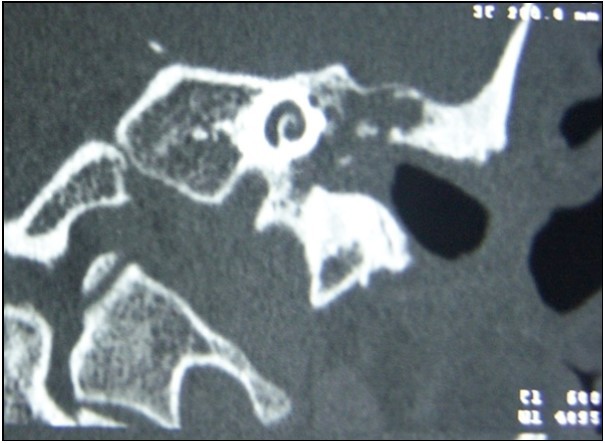

All preoperative CT scans included soft tissue in tympanic cavity, 23 (69.7%) of them demonstrated bone tissue erosion whereas 10 (30.3%) of them did not (Figure 2) (Table 1).

18 of 23 (78.3) patients who had bone erosions on CT images were observed to have cholesteatoma intraoperatively while the remaining 5 (21.7) were not. Cholesteatoma was detected in 7 of 10 (70%) patients who did not have any sign of bone destruction on CT and remaining 3 (30%) of them were negative (Table 2). No significant result was obtained in terms of impact of tomographic view of bone erosions on indicating presence of intraoperative cholesteatoma (p=0,61)

Figure 2.Soft tissue image causing bone erosion on temporal CT